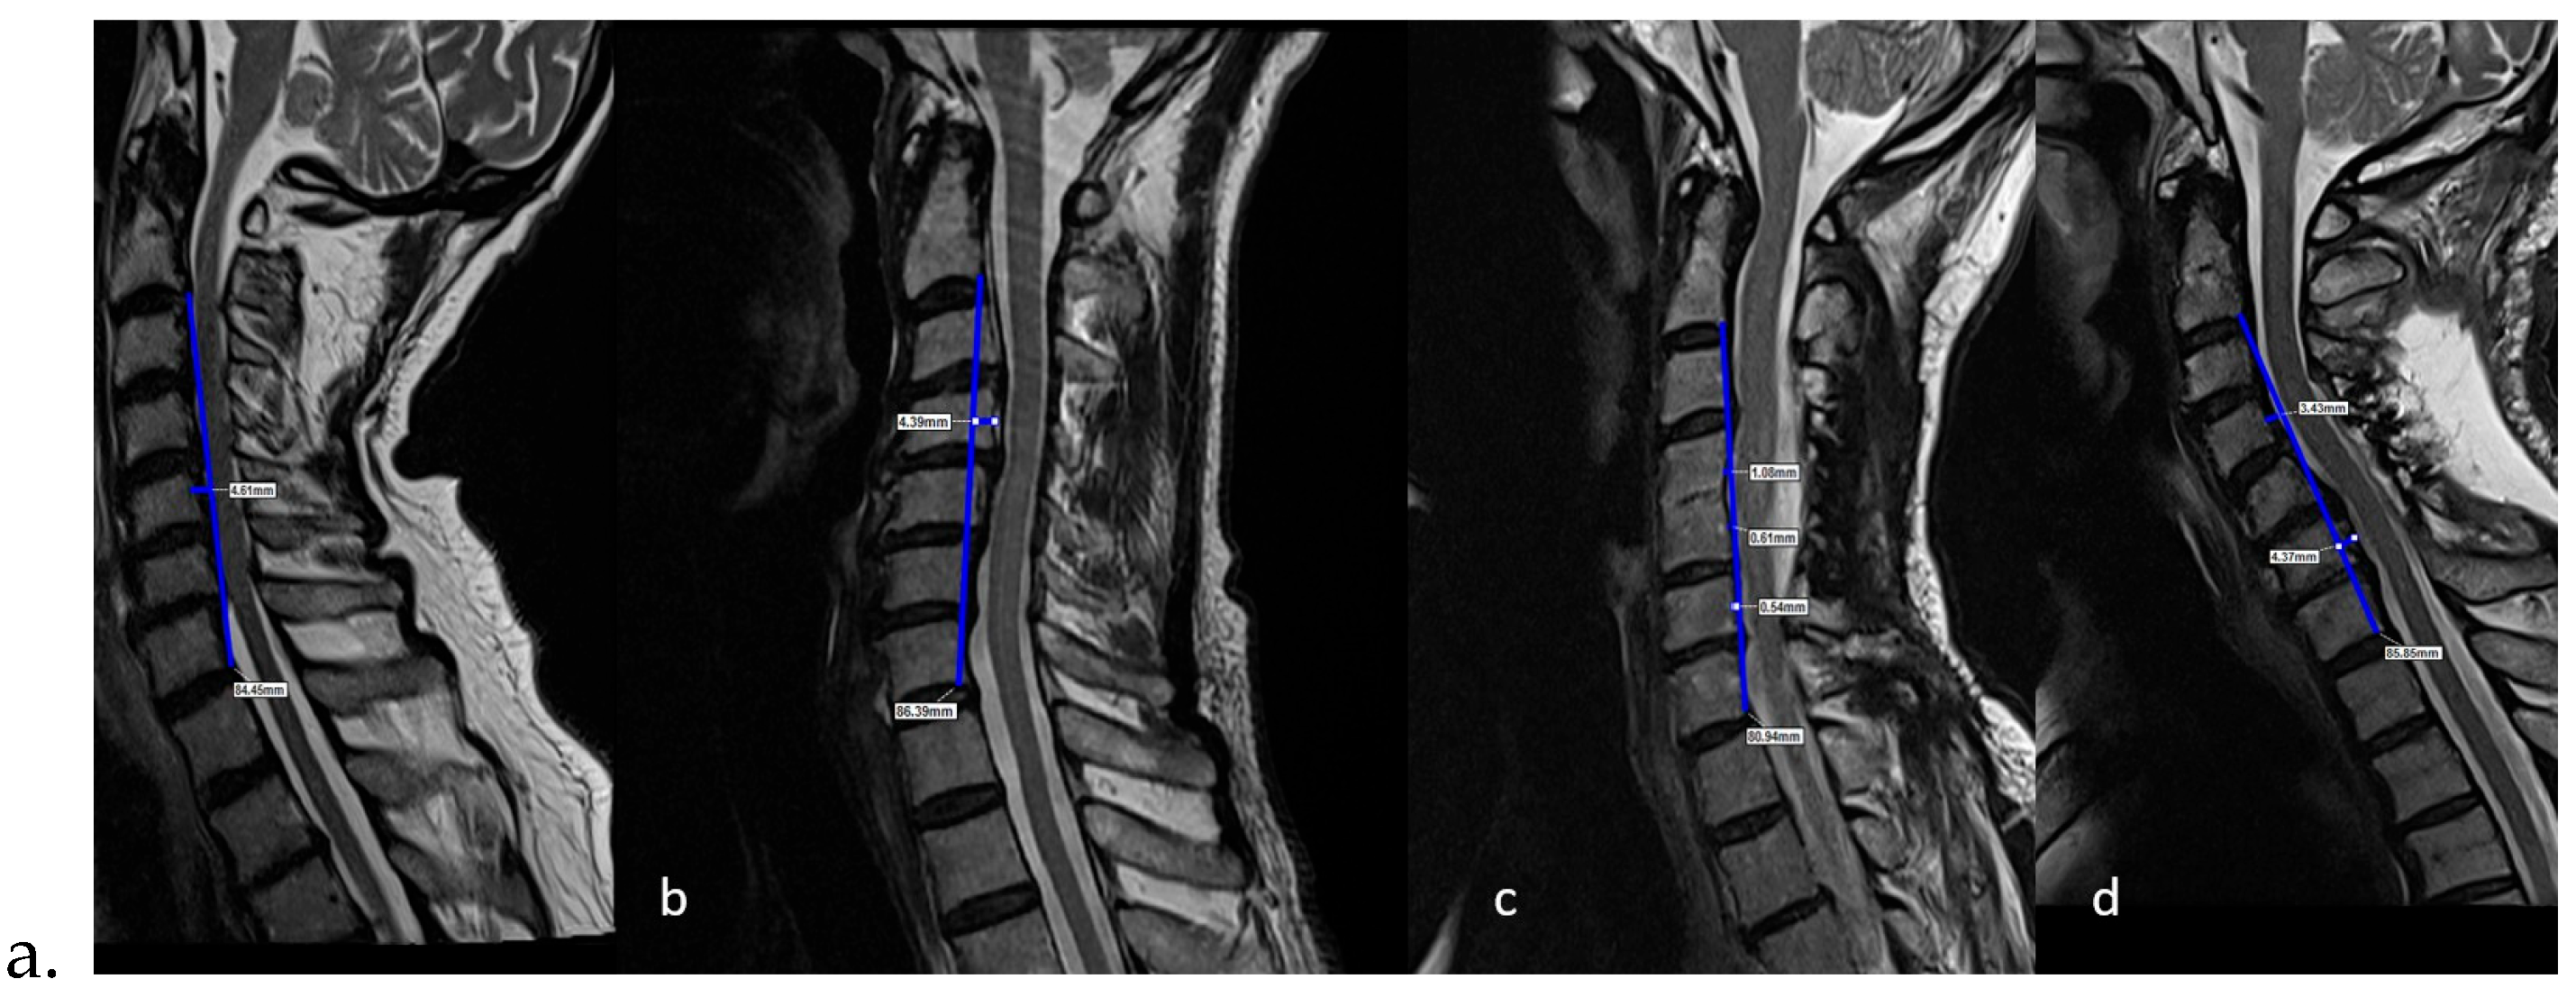

2.3. Dependent Variables (Radiological)

- Postoperative last control C2–C7 Cobb angle

- Postoperative last control cervical alignment

- Postoperative last control K-line

Preoperative C2–C7 Cobb Angle vs. Postoperative Last Control C2–C7 Cobb Angle

Preoperative Cervical Alignment Category vs. Postoperative Cervical Alignment Category

Preoperative K-Line vs. Postoperative K-Line